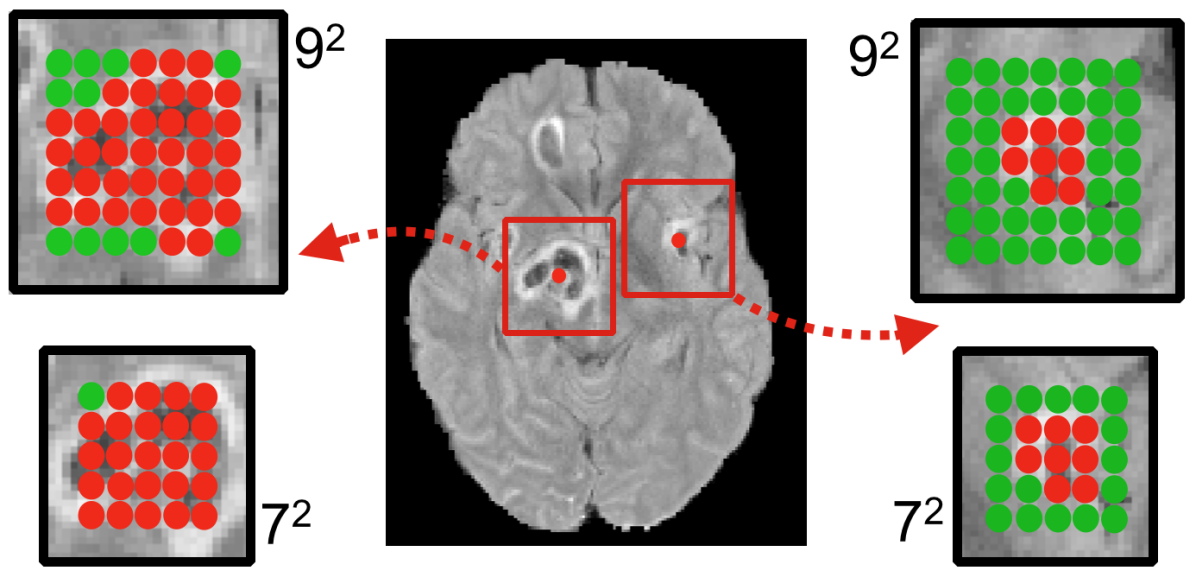

3.4 Effect of the Multi-Scale Dual Pathway

Refer to caption

Figure 8: Mean accuracy over validation samples and DSC for the segmentation of the validation images, as obtained by a single-scale model (Deep+) and our dual pathway architecture (DeepMedic). We also trained a single-scale model with larger capacity (BigDeep+), similar to the capacity of DeepMedic. DeepMedic yields best performance by capturing greater context, while BigDeep+ seems to suffer from over-fitting.

The final version of the proposed network architecture, referred to as “DeepMedic”, is built by extending the Deep+ model with a second convolutional pathway that is identical to the first one. Two hidden layers are added for combining the multi-scale features before the classification layer, resulting in a deep network of 11-layers (cf. Fig. 5). The input segments to the second pathway are extracted from the images down-sampled by a factor of three. Thus, the network is capable of capturing context in a 513superscript51351^{3} area of the original image through the 173superscript17317^{3} receptive field of the lower-resolution pathway, while only doubling the computational and memory requirements over the single pathway CNN. In comparison, the most recent 2D CNN systems proposed for lesion segmentation (Havaei et al. (2015); Pereira et al. (2015)) have a receptive field limited to 332superscript33233^{2} voxels.

Figure 9: (Rows) Two cases from the severe TBI dataset, showing representative improvements when using the multi-scale CNN approach. (Columns) From left to right: the MRI FLAIR sequence with the manually labeled lesions, predicted soft segmentation map obtained from a single-scale model (Deep+) and the prediction of the multi-scale DeepMedic model. The incorporation of greater context enables DeepMedic to identify when it processes an area within larger lesions (top). Spurious false positives are significantly reduced across the image on the bottom.

Figure 8 shows the improvement DeepMedic achieves over the single pathway model Deep+. In Fig. 9 we show two representative visual examples of this improvement when using the multi-scale CNN. Finally, we confirm that the performance increase can be accounted to the additional context and not the additional capacity of DeepMedic. To this end, we build a big single-scale model by doubling the FMs at each of the 9-layers of Deep+ and adding two hidden layers. This 11-layers deep and wide model, referred to as “BigDeep+”, has the same number of parameters as DeepMedic. The performance of the model is not improved, while showing signs of over-fitting.